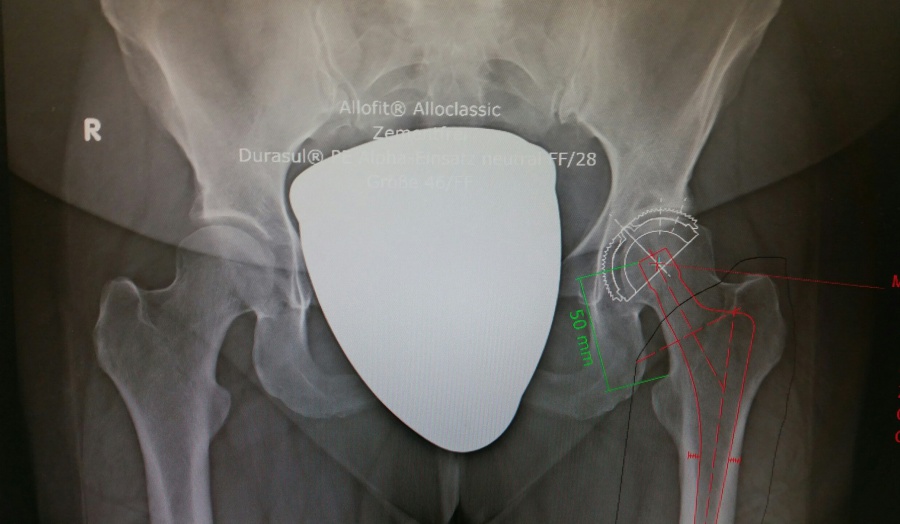

Hüftarthrose links, Planungsbild vor dem Gelenkersatz

Ein künstliches Hüftgelenk besteht aus einer Pfanne, einem Pfanneneinsatz aus hochwertigem Kunststoff oder Keramik, einem Metall- oder Keramikkopf und einem Schaft. Diese Komponenten zeigen das gewünschte geringe Abriebverhalten. Die Pfanne kann durch einen schnell härtenden Kunststoff (Knochenzement) oder zementfrei mit dem Knochen verbunden werden. Bei zementfreien Pfannen muss der Knochen erst langsam in die raue Titanoberfläche des Metalls einwachsen. Die Verankerung des künstlichen Schaftes im Oberschenkelknochen erfolgt entweder durchlangsames Einwachsen des Knochens in die Metalloberfläche der Prothese oder mit Hilfe des Knochenzements.

In Regionalanästhesie oder Allgemeinnarkose wird das Hüftgelenk freigelegt, der Hüftkopf entfernt und die Gelenkpfanne sowie der Oberschenkelknochen für den Einsatz der beiden Prothesenteile vorbereitet.

Vor der Operation wird nach gründlicher Planung die Wahl der Endoprothese sowie der Verankerungsmethode getroffen. Dabei werden Alters- und Hüftsituation des Patienten berücksichtigt.